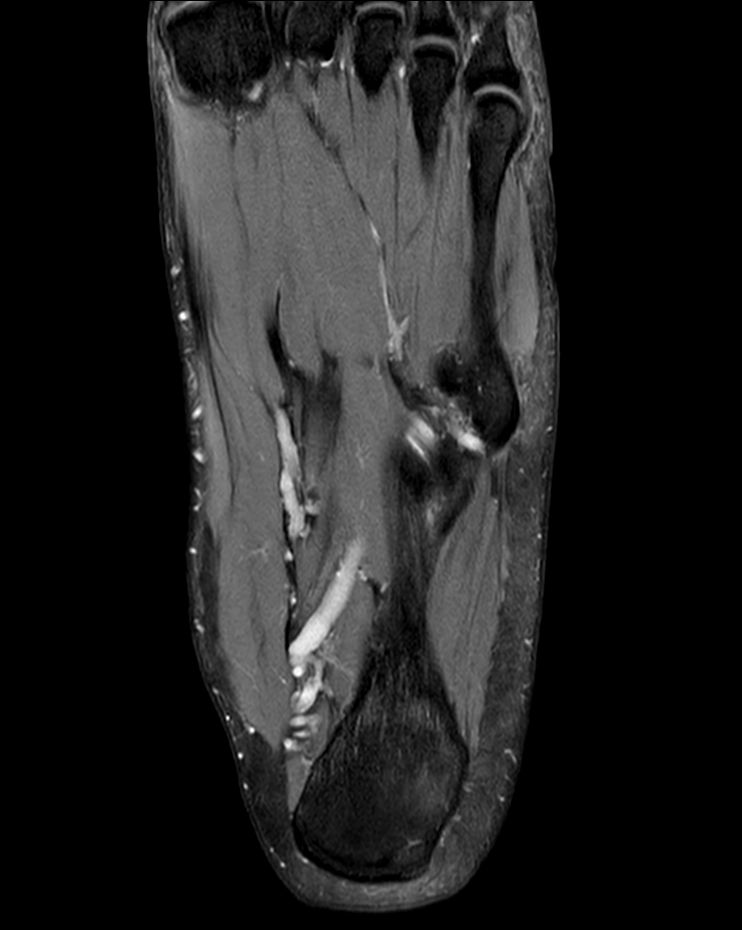

Foot with plantar fascitis

Coronal PDw TSE mDIXON XDCompressed SENSE